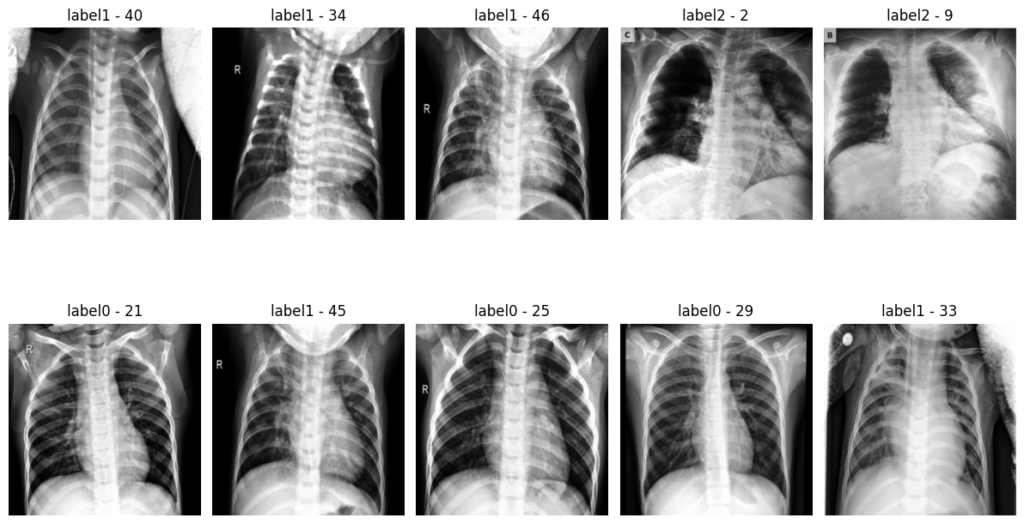

Dataset after resize transformation and standardization: